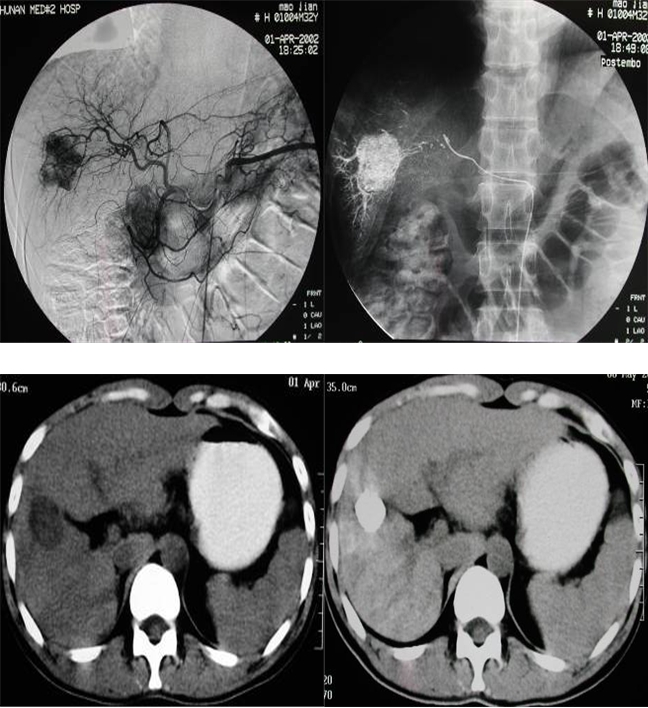

肝癌介入治疗前后造影及CT疗效对比